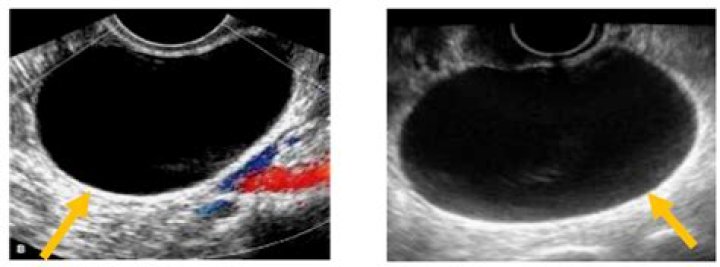

A simple cyst typically is round or oval, anechoic, and has smooth, thin walls. It contains no solid component or septation (with rare exceptions), and no internal flow is visible on color Doppler imaging. Cyst

By definition, flow towards the transducer is depicted in red while flow away from the transducer is shown in blue. Different shades of red and blue are used to display velocity. Lighter shades of color are assigned to higher velocities.

Ultrasound. Corpus luteum cysts are typically unilocular, usually less than 3 cm in diameter and diffusely thick-walled with prominent peripheral blood flow (“ring of fire” on Doppler). The cysts may be crenulated or contain low-level internal echoes (Figs.

Do cysts show blood flow on ultrasound?